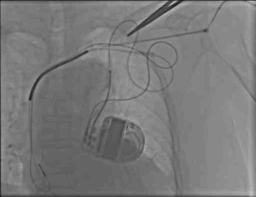

病例一

Metronic 4296 双阴极电极,6248辅助鞘

手术过程